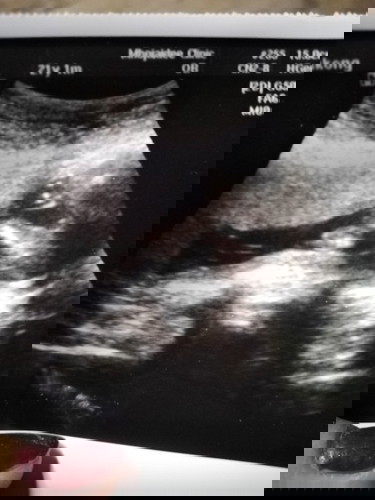

แม่ๆช่วยดูหน่อยค้ะว่าชายหรือหญิง

ชายหรือหญิงค้ะช่วยดูหน่อยค้ะ☺☺

ดูไม่ออกเลยค่ะเหมือนจะมีโผล่ๆเเต่ไม่เเน่ใจ

หม่าม๊า of 1 ตัวแสบ คุณชาย